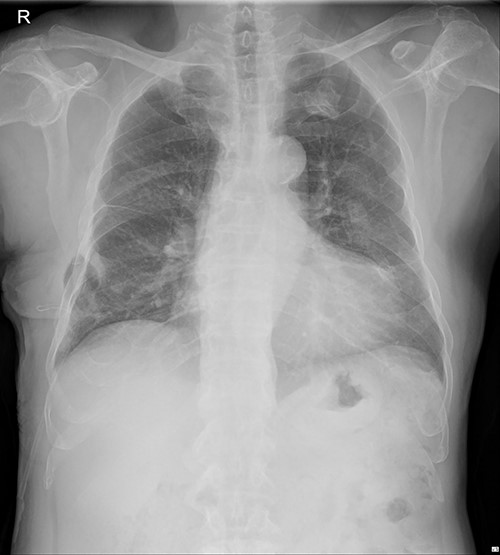

The submuscular emphysema, however, was increased in size, and the patient was eventually re-hospitalized. A small incision was made beneath the surgical wound under local anesthesia, and a 10 FR thoracic drainage catheter was carefully placed into the submuscular layer (Fig. 4.). Under 2 L of oxygen supplement, the submuscular emphysema gradually decreased over several days, and the patient was finally discharged on hospital Day 6 (Fig. 5). Since his last readmission, there have not been any more complications.

Chest X-ray after applying a 10 FR drainage thoracic catheter into the submuscular layer (11 March 2022).